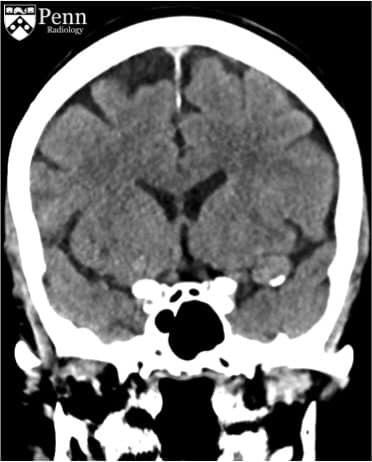

Paciente femenina de mediana edad que acude al servicio de urgencias por presentar convulsiones por primera vez, tras realización de CT de craneo se obtienen las siguientes imagenes:

La lesion evidenciable se encuentra:

a) extraxial

b) intraxial

Probable estirpe etiologica de la lesion:

a) glial

b) dural

c) vascular

d) ependimaria

Las areas hiperdensas sugieren?:

a) sangrado activo

b) sangrado antiguo

c) calcificaciones vasculares

d) fragmentos oseos